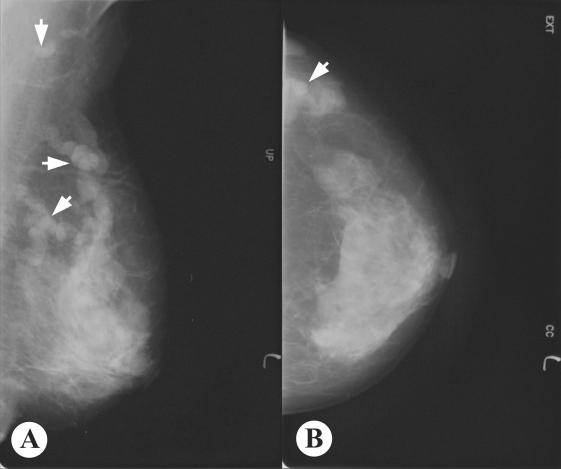

AbstractA case of breast sparganosis was confirmed by surgical excision of a worm (fragmented into 5 pieces) in a 59-year-old Korean woman suffering from a palpable mass in the left breast. Mammography and ultrasonography characteristically revealed the presence of several well-defined, isodense and hypoechoic tubular masses, in the upper quadrant of the left breast, each mass consisting of a continuous cord- or worm-like structure. During surgery, a long segment of an actively moving sparganum of Spirometra sp. and 4 small fragments of the same worm, giving a total length of 20.3 cm, were extracted from the upper outer quadrant of the left breast and the axillary region. The infection source remains unclear, because the patient denied ingesting any snake or frog meat or drinking untreated water. INTRODUCTIONSpargana are the plerocercoid larvae of a pseudophyllidean tapeworm that belongs to the genus Spirometra (Beaver et al., 1984). These larval tapeworms only very rarely grow to the adult stage in the human body (Lee et al., 1984), but the larval stage can cause an infection, namely, human sparganosis (Cho et al., 1974, 1975). Human sparganosis is contracted by eating raw or improperly cooked flesh of snakes or frogs infected with the plerocercoid larvae, by topically applying snake or frog skin to sore eyes, or drinking water contaminated with cyclops harboring the procercoid larvae (Beaver et al., 1984). Human sparganosis cases are reported worldwide, but are more common in Asia, particularly Korea, China, Japan, Taiwan, Vietnam, and Thailand (Beaver et al., 1984). In Korea, 3 human cases were reported for the first time in 1924 (Kobayashi, 1925), but more than 100 cases were subsequently documented before the end of the 1980s in the Republic of Korea (Cho et al., 1975; Min, 1990). The patients were distributed nationwide, although more cases were reported in the northern parts of the Republic of Korea (Min, 1990). Moreover, seroepidemiologic observations in the normal adult population and in epileptic patients revealed high antibody positivities of 1.9% and 2.5%, respectively (Kong et al., 1994). The major reasons why snake meat is consumed in the Republic of Korea are due to the misconception that snake meat is an aphrodisiac, and because it is viewed as field food during military survival training (Cho et al., 1974, 1975; Min, 1990). Radiological (Chung et al., 1995; Kim et al., 2005; Koo et al., 2006) and serological (Kong et al., 1994) techniques can provide useful diagnostic clues of sparganosis. However, in the case of breast sparganosis, radiological images closely resemble those of a neoplasm or granulomatous mastitis (Jeong et al., 1995; Chung et al., 1995; Moreira et al., 1997; Kim et al., 2005). Nevertheless, if a case shows characteristic, though not specific, mammography and ultrasonography findings, these helpfully raise suspicions of breast sparganosis. We encountered an interesting case of breast sparganosis that showed characteristic mammography and ultrasonography findings. The diagnosis was later confirmed by surgical excision of the worm. CASE RECORDA 59-year-old Korean woman, a housewife residing in Seoul, with palpable masses in the left breast of 2 years duration, visited a local clinic, and was suspected as having a soft tissue tumor. She was transferred to a university hospital and then to the Korea Cancer Center Hospital. The patient had a clinical history of hormone replacement therapy some 10 years previously. Except for the palpable breast masses, physical examinations revealed no other abnormalities. She had a good consciousness and nutritive condition, and routine hematological, urinal, and chemical investigations were normal. No active lesion was observed by chest X-ray. Mammography showed multiple, well-defined, isodense, lobular, and continuous cord-like structures in the upper outer quadrant of the left breast (Fig. 1). Ultrasonographic findings also showed well-defined, hypoechoic, tubular masses with folded band-like tracts and a tubule-in-tubule appearance, in the parenchymal layer of the left breast (Fig. 2). A neoplastic disease could not be ruled out, and therefore, fine needle aspiration biopsy was performed on the breast mass, which showed no evidence of neoplastic diseases. Then, breast sparganosis was suspected. For an etiological diagnosis and treatment, left breast tissue was surgically excised. In resected tissue, a lesion with focal fibrosis, without definite mass formation, was observed and histopathologically confirmed as a fibrocystic disease. In the left side of the fibrotic cyst, a long tapeworm segment (Fig. 3), 12.0 cm × 0.7 cm in size, was found across the upper outer quadrant of the left breast toward the axillary region, and carefully extracted. The presence of a scolex was confirmed in this segment. In addition, 4 more fragments of the same worm of 3.3 × 0.8 cm, 1.7 × 0.7 cm, 1.6 × 0.8 cm, and 1.7 × 0.8 cm (Fig. 3), were collected from around the fibrotic cyst. All 5 extracted segments showed active movement, and were fixed in 10% buffered neutral formalin solution for morphological identification. The worm was identified as a sparganum of Spirometra sp., and had a total length of 20.3 cm. The patient denied ingesting snake and frog meat, and drinking untreated water. DISCUSSIONSpargana have the ability to migrate to any part of the human body (Cho et al., 1975; Min, 1990), including the brain (Anders et al., 1984) and oral cavity (Iamaroon et al., 2002). However, predilection sites include the abdomen (38 cases; 28.1%), urogenital organs (30; 22.2%), extremities (24; 17.8%), central nervous system (16; 11.9%), chest (14; 10.4%), and the orbital region (11; 8.1%); based on an analysis of 135 cases reported before 1987 in the Republic of Korea (Min, 1990). Breast sparganosis is rare, i.e., only 2 of these 135 cases (Jung et al., 1981; Nha et al., 1987). However, since 1987, 18 breast cases have been reported (Chi et al., 1988; Choi et al., 1992; Lee et al., 1992; Park and Hwang, 1992; Jeong et al., 1995; Chung et al., 1995; Park et al., 1996; Chang et al., 2000; Sim et al., 2002; Kim et al., 2003). Therefore, the present case becomes the 21st reported case of breast sparganosis in the Republic of Korea; reported cases are briefly summarized in Table 1. Sparganosis cases with fragmented worm segments in tissue, as in the present case, are uncommon, though infections with multiple worms are not uncommon. Seo et al. (1964) reported a case with 3 worms in the left lower scrotal area, where spargana are frequently found. Park et al. (1986) also observed a case with 4 worms in the scrotum and inguinal region. Cho et al. (1975) reviewed 60 sparganosis cases; 44 had only one worm, 6 with 2 worms, 4 with 3 worms, and the remaining 6 had 4-12 worms. However, in cases of breast sparganosis, only 1 worm has been reported in most patients (Table 1). In our case, 5 worm segments were recovered from the upper quadrant of the left breast and axillary region. All of these segments were actively motile after excision, and thus initially we believed that there were 5 distinct worms. However, careful observation confirmed them to be worm segments from a single worm, the longest of which was equipped with the scolex and neck portion (Fig. 3). With regard to the source of infection, Min (1990) summarized the past histories of sparganosis patients and noted that the majority of patients had experience of eating various kinds of animal fleshes including snakes and frogs, and that some of the patients had drank untreated water. Moreover, although the likelihood of drinking untreated water is probably similar for men and women, the eating of snakes or frogs is likely to be far more common in men, which concurs with a known disease gender preference, i.e., men, 94 of 119 cases, and women, 25 of 119 cases (Min, 1990). With regard to breast sparganosis, patients reported in the Republic of Korea to date have all been females. Moreover, the majority have denied eating snake or frog meat, which leaves the source of infection in these cases obscure (Table 1). Also in the present case, the mode of infection was unclear, since the patient denied eating any snake or frog meat or drinking untreated water. Thus, the source of sparganum infection in female patients without a history of exposure to known sources should be clarified. Breast sparganosis presents as soft tissue nodules, as in the present case, and is confused with neoplastic masses in radiological images (Chuen-Fung and Alagaratnam, 1991; Jeong et al., 1995). For example, its mammographic features are usually multiple, lobular, marginated, amorphic, and solid masses without calcifications, which are similar to the features of the circumscribed breast cancer or benign tumor-like fibroadenoma (Chung et al., 1995; Kim et al., 2005). Thus, a confirmatory diagnosis should be established by extracting the worm responsible or by examining surgical pathology specimens. However, as shown in the present case, mammography findings can be characteristic and highly useful for a pre-operative diagnosis of breast sparganosis. Ultrasonographic findings may also be useful for the pre-operative diagnosis of breast or other organ sparganosis (Chung et al, 1995; Cho et al., 2000; Kim et al., 2005). In breast sparganosis, elongated, folded, band- or tunnel-like hypoechoic tubular structures in heterogenous, hyperechoic masses are characteristic (Chung et al., 1995), whereas in subcutaneous and musculoskeletal sparganosis, serpiginous, cystic, tubular tracts, with internal anechogenicity and posterior echo enhancement, are important characteristics (Cho et al., 2000). Intraluminal lesions formed by the larvae or debris and peritubular echo changes produced by chronic inflammatory reactions have been noted in a half of musculoskeletal sparganosis cases (Cho et al., 2000). However, findings of elongated, serpiginous, and tubular structures may also be obtained in other types of diseases, such as, ectatic ducts, radiation edema, superficial thrombophlebitis, and congestive heart failure (Chung et al, 1995; Kim et al., 2005). Nevertheless, such findings together with high antibody titers against sparganum, and characteristic mammography and ultrasonography findings will be very useful for a pre-operative diagnosis of sparganosis. REFERENCES1. Anders K, Foley K, Stern WE, Brown WJ. Intracranial sparganosis: an uncommon infection. J Neurosurg. 1984. 60:1282-1286.      2. Beaver PC, Jung RC, Cupp EW. Clinical Parasitology. 1984. 9th ed. Philadelphia, U.S.A.: Lea & Febiger; 499-504. 3. Chang YK, Kim KC, Cho HJ. Sparganosis in the female breast. J Korean Surg Soc. 2000. 58:285-287 (in Korean). 5. Cho JH, Lee KB, Yong TS, Kim BS, Park HB, Ryu KN, Park JM, Lee SY, Suh JS. Subcutaneous and musculoskeletal sparganosis: imaging characteristics and pathologic correlation. Skeletal Radiol. 2000. 29:402-408.      6. Cho SY, Ahn GH, Ro JY, Hahn JH. Two cases of sparganosis caused by survival training in army. J Korean Med Ass. 1974. 17:367-371 (in Korean). 7. Cho SY, Bae JH, Seo BS. Some aspects of human sparganosis in Korea. Kisaengchunghak Chapchi. 1975. 13:60-77.      8. Choi YH, Oh HJ, Jeong YK, Lee SC. A case of multiple spargana in female breast. J Korean Surg Soc. 1992. 43:300-304 (in Korean). 10. Chung SY, Park KS, Lee Y, Park CK. Breast sparganosis: mammographic and ultrasound features. J Clin Ultrasound. 1995. 23:447-451.      11. Iamaroon A, Sukontason K, Sukontason K. Sparganosis: a rare case of the oral cavity. J Oral Pathol Med. 2002. 31:558-560.      12. Jeong JK, Ryu BY, Lee HW, Kim HK, Choi CS. Sparganosis of the breast. J Korean Surg Soc. 1995. 48:428-432 (in Korean). 13. Jung PJ, Yoo BO, Park CY, Koo BH. A case of human sparganosis in the breast. J Korean Surg Soc. 1981. 23:269-271 (in Korean). 14. Kim HS, Cha ES, Kim HH, Yoo JY. Spectrum of sonographic findings in superficial breast masses. J Ultrasound Med. 2005. 24:663-680.    15. Kim YS, Hwang MS, Lee JK, Kim DS, Lee SK. US findings of breast sparganosis. J Korean Soc Med Ultrasound. 2003. 22:151-156 (in Korean). 16. Kobayshi H. On the animal parasites in Korea. Japan Med World. 1925. 5:9-16 (in Japanese). 17. Kong Y, Cho SY, Kang WS. Sparganum infections in normal adult population and epileptic patients in Korea: a seroepidemiologic observation. Korean J Parasitol. 1994. 32:85-92.     18. Koo JH, Cho WH, Kim HT, Lee SM, Chung BS, Joo CY. A case of sparganosis mimicking a varicose vein. Korean J Parasitol. 2006. 44:91-94.        19. Lee BJ, Ahn SK, Kim SC, Lee SH. Clinical and histopathologic study of sparganosis. Korean J Dermatol. 1992. 30:168-174 (in Korean). 20. Lee SH, Chai JY, Seo BS, Cho SY. Two cases of human infection by adult of Spirometra erinacei. Korean J Parasitol. 1984. 22:66-71.     22. Moreira MA, de Freitas Jr. R, Gerais BB. Granulomatous mastitis caused by sparganum. A case report.. Acta Cytol. 1997. 41:859-862.    23. Nha SG, Cho WH, Lim TJ, Park YK. A case of sparganosis in female breast. J Korean Surg Soc. 1987. 32:473-475 (in Korean). 24. Park CK, Hwang WC. Sparganosis of the breast: a case report. Human Sci. 1992. 16:327-330 (in Korean). 25. Park JM, Hwang JC, Choi YB. Sparganosis of the breast. J Korean Radiol Soc. 1996. 34:843-845 (in Korean). 26. Park JY, Choi YS, Yeum KY, Ahn DH. A case of sparganosis infecting on the scrotum and inguinal area. J Koryo General Hosp. 1986. 9:185-187 (in Korean). Fig. 1Mammogram of the present breast sparganosis case. A: Mediolateral oblique view, B: Craniocaudal view. Welldefined, isodense, lobular, and continuous cord-like structures (arrows) were characteristically observed in the upper outer quadrant of the left breast.   Fig. 2Ultrasonograms of the present sparganosis case, showing a well-defined hypoechoic, tubular mass with internal heterogeneous echogenicity, and tubule-in-tubule appearance in the subcutaneous layer of the upper outer quadrant of the left breast.   Fig. 3Segments of the sparganum obtained by surgical removal. A long segment with a scolex (arrow) was extracted across the left breast to the axillary region. The other 4 segments were collected from lumps in the same left breast.   Table 1.Breast sparganosis cases reported in the Republic of Korea